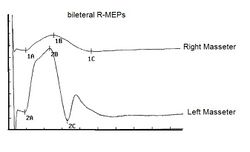

b) Stimolazione Transcraniale Magnetica della corteccia trigeminale (STM) - La posizione del coil fu leggermente anteriorizata rispetto a Cz ed il paziente manteneva per almeno 5 Sec una moderata attività muscolare stringendo i denti. L’impulso fu massimale 100% della potenza dello stimolatore e le risposte furono registrate simultaneamente su ambedue i masseteri.

La figura 11 mostra le risposte masseterine alla STM corticale e possiamo distinguere: una risposta diretta (figura 11-1) della radice trigeminale di destra; una risposta di difficile interpretazione (figura 11-2) che preferiamo definire sconosciuta ma che con buona probabilità può essere dovuta alla stimolazione diretta delle fibre Ia a livello intracranico; una risposta integralmente corticale (figura 11-3) che rappresenta la volley delle fibre corticobulbari trigeminali con una latenza di @8 mS dovuta al lungo percorso delle vie corticobulbari ed al ritardo centrale; un silenzio elettrico (figura 11-4) dovuto principalmente alla sincronizzazione dei motoneuroni di II ordine e/o probabilmente alla stimolazione del ramo nocicettive del tratto spinale trigeminale. Da notare la perfetta simmetria in ampiezza delle risposte motorie evocate corticali .

Fig.11: Potenziali Evocati Motori Corticali generati dalla Stimolazione Magnetica Transcraniale. Per ulteriori dettagli vedere testo